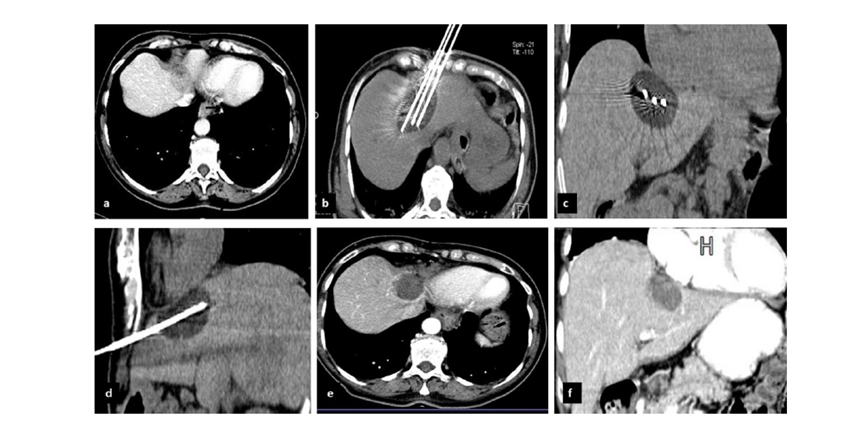

79 岁男性,肝转移(结直肠癌)肿瘤的完全消融病例

( a ) 轴向 MRI 和 ( b ) 轴向 CT 显示肝S8段有一个16mm的病灶,邻近肝缘。

( c )冷冻消融期间CT显示放置了2个冷冻探针,低密度冰球包围病灶。

(d)术后1个月随访 CT显示冰球对应的坏死区域,未见复发。

(e)术后6个月的CT,坏死区域缩小,未见复发。

(f)与基线影像(g)相比,12个月后的FDG-PET/CT显示未见FDG摄取。

62岁女性,肝转移(卵巢癌)肿瘤的完全消融病例

(a)轴向CT显示病变位置毗邻心脏和上腔静脉(黑色箭头)。

(b)术中轴向CT扫描:使用三个冷冻探针。

(c)冠状面和(d)矢状面显示冰球毗邻心包。

1个月后的轴向(e)和冠状位(f)增强CT扫描显示低密度区域,由于肉芽组织反应引起的边缘增强。